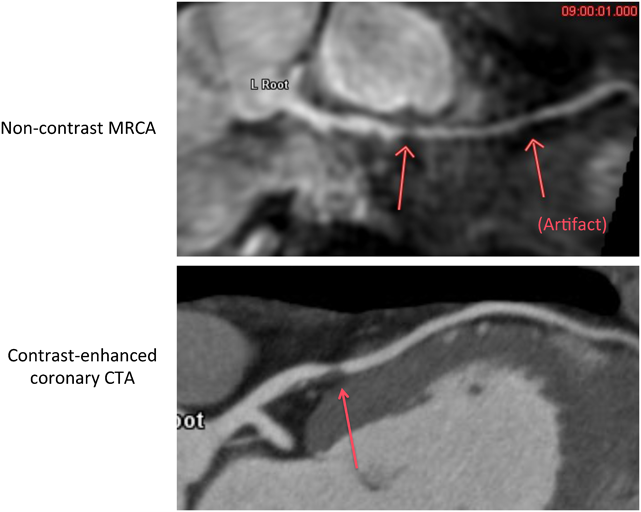

③非造影MRA

MRAはMR angiographyの略で,その名の通りMRIで血管を描出する撮影プロトコールである.成人循環器領域で最も患者の多い冠動脈疾患の診断を最大の目的として技術的革新が進んだ.MRIは組織間コントラストが非常に優れており,冠動脈MRA(MRCA)では造影剤を使用しなくても血液を白く光らせ,冠動脈を明瞭に描出することが可能である.MRCAの撮影技術は,2003年に開発された比較的新しいMRI撮影技術である,世界的に見ても安定して実施できる医療機関はまだ限られている.心臓CTよりも低侵襲(ほぼ無侵襲)であり,原理的特徴から冠動脈石灰化による影響を受けずに血液を高信号に描出し冠動脈内腔を描出可能である.MRCAは心臓CT検査のような呼吸停止が不要で,普通に呼吸した状態(free breath)で,横隔膜同期および心電図同期を併用して撮影する(Fig. 6).そのため,呼吸停止の困難な方や耳の不自由な方にとっても比較的容易にできるのが特徴である.Fig. 7はこのプロトコールで撮影した成人冠動脈(左前下行枝)である.segment 7に明瞭な信号低下が認められ,有意狭窄が疑われた.同一症例の造影CTAが下図である.空間分解能にまさる冠動脈造影CTではより明瞭に非石灰化プラークの形状まで描出され,同部位に有意狭窄が存在することが確認された.このように本プロトコールでは非造影にて,診断に使えるレベルの冠動脈形態が描出可能である.非造影MRAによる冠動脈狭窄の陽性的中率はおよそ70%,陰性的中率は96%と低侵襲でスクリーニングに長じた結果が示されている39)

Pediatric Cardiology and Cardiac Surgery 32(4): 291-306 (2016)

Fig. 6 Navigator-gated free breathing MRCA

MRCA: magnetic resonance coronary angiogram.

Fig. 7 Non-contrast MRCA and contrast-enhanced coronary CTA

MRCA: magnetic resonance coronary angiography; CTA: computed tomography angiography.